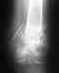

Здравствуйте! Моё имя Юлия мне 28лет, в июля 2008г у меня был оскольчатый перелом нижней трети правой плечевой кости со смещением.

Был сделан остеосинтез инстрамедулярным штифтом и блокирующим винтом.

В 2009г. винт был удалён т,к, была боль при поднятии руки, штифт доставать не стали.У меня сахарный диабет 1 типа с детства, скажите пожалуйста нужно ли удалять штифт, насколько опасна данная операция, и есть ли какие-то негативные последствия если штифт оставить? (слышала, что если понадобится томограмма, её не делают людям у кого остеосинтез)